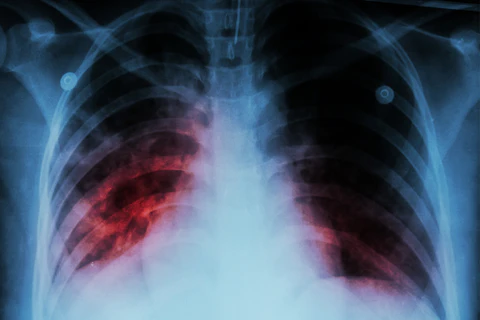

Kajian dijalankan oleh saintis di Sweden yang diterbitkan dalam BMJ baru-baru ini dimana, mereka melakukan perbandingan di antara 1 juta individu yang pernah dijangkiti covid dengan 4 juta individu yang tidak dijangkiti covid, daripada perbandingan tersebut, angka yang mendapat masalah pulmonary embolism meningkat 33 kali ganda bagi mereka yang pernah dijangkiti covid samaada simptomnya mild atau serius. Selain daripada pulmonary embolism, kita juga berhadapan dengan deep venous thrombosis, iaitu melibatkan salur darah pada bahagian kaki, kadang-kadang bahagian dalam vein itu akan tersumbat oleh darah beku, dan kita tak rasa sangat sebab simptomnya cuma bengkak kaki, sakit, merah. Dan masalah ini sebenarnya meningkat 5 kali ganda jika dibandingkan dengan mereka yang tidak dijangkiti covid.

Sewaktu dijangkiti covid juga boleh meningkatkan risiko strok sehingga 2 bulan selepas dijangkiti, masalah paru-paru pula sehingga 6 bulan selepas dijangkiti. Ada juga kajian menunjukkan bahawa jangkitan covid yang disertai dengan simptom yang ringan boleh meningkatkan risiko untuk mendapat pulmonary embolism sebanyak 7 kali ganda. Tetapi, seandainya simptom covid itu serius , ia boleh meningkatkan risiko sebanyak 290 kali ganda pulmonary embolism. Risiko-risiko lain termasuklah cardiovascular disease seperti heart disease, ischemia yang mana risikonya meningkat sebanyak 63%, manakala risiko strok pula adalah sebanyak 52%.

Pulmonary bermaksud paru-paru. Embolism pula darah beku yang wujud pada salur darah yang besar, tapi sedikit demi sedikit ia keluar dan pecah kepada fragment-fragment yang kecil, dan ini akan dialirkan ke aliran darah dan sampai ke satu tahap ia akan tersumbat di bahagian paru-paru. Contohnya mungkin darah beku itu berlaku di bahagian betis kita, tapi ia kemudiannya berpecah ke dalam aliran darah sehingga sampai ke bahagian paru-paru.